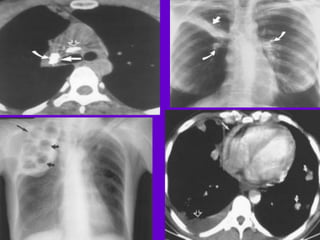

CT Scan and MRI Scan in the

diagnosis of TB

􀂄 The advent of CT and MRI imaging in

the last two

decades has redefined the approach in

analysis of

various diseases including TB.*

􀂄 CT and MRI have shown several

advantages over

conventional radiology in early diagnosis

and follow-up

of TB in different parts of the body.

Pulmonary TB :

􀂄Lobar Pneumonia

􀂄 CT is superior than plain CXR in picking

up the

consolidation, atelectasis and the hilar LN

thereby

making the diagnosis easy.

􀂄 MRI reveals some of these changes,

however, CT is

the diagnostic modality of choice in such

cases.

Hilar and Mediastinal

Lymphadenopathy

􀂄 CT and MRI depict the hilar and

mediastinal LN

equally well.

􀂄 Calcification in the nodes is however

better seen on

CT.

􀂄 Necrosis is seen as focal areas of low

attenuation on

a CECT.

􀂄 On MRI focal necrosis is seen as areas

of increased

signal intensity on T2W images.

􀂄EBTB

􀂄 HRCT is sensitive in the detection of

early

endobronchial spread of disease.